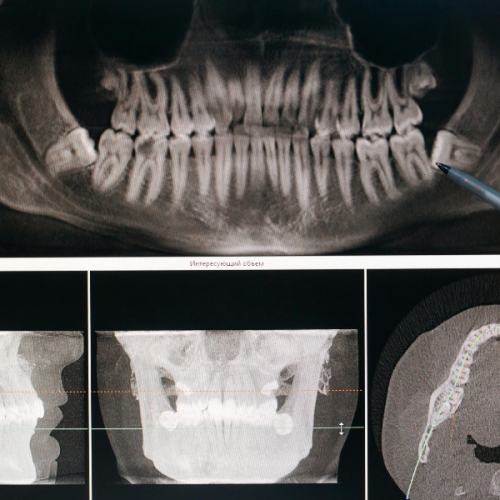

At Dantaa Dental Clinic, we will start with a thorough evaluation to find out where your wisdom teeth are located through either X-rays or 3D imaging. This helps patients understand the condition clearly, especially those visiting us for wisdom teeth removal in Chandigarh.

- Bony Impaction: The most complex category, where the tooth is completely or partially within the jawbone as shown by dental experts.

These types are essential for determining treatment plans and understanding the wisdom teeth removal cost.